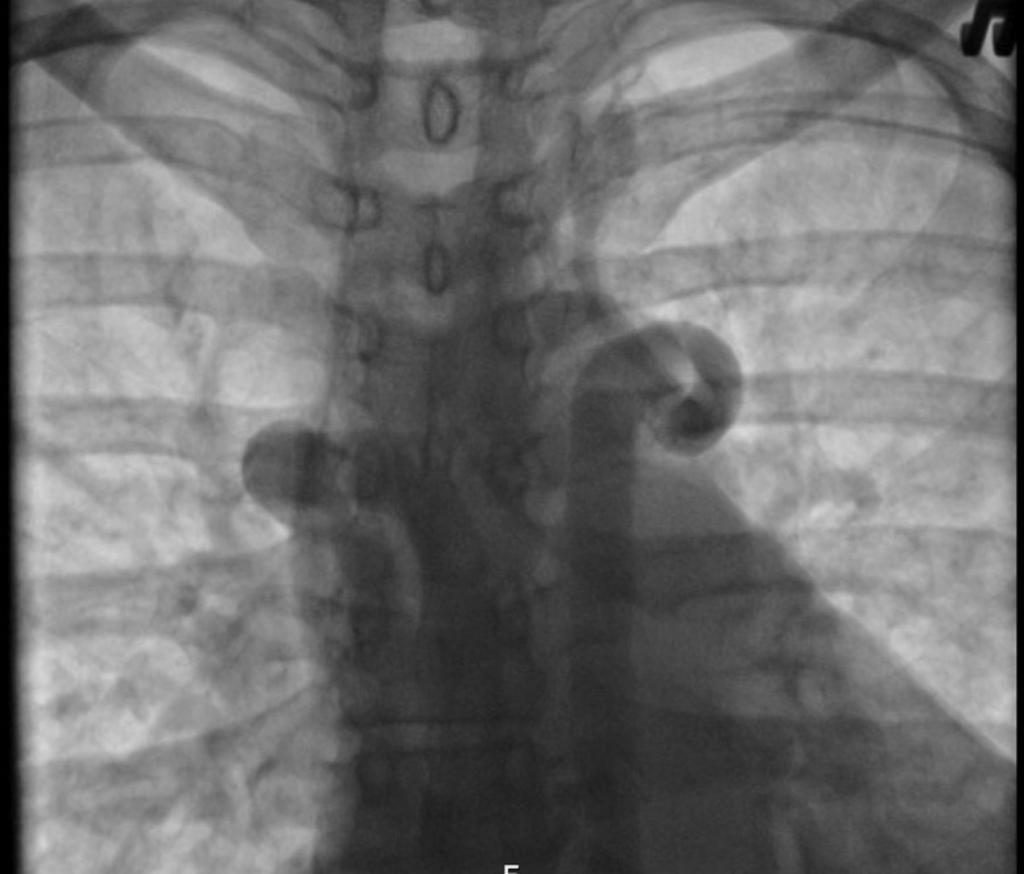

Рентген снимок атипичной пневмонии

Атипичная пневмония — собирательный термин, включающий инфекционно-воспалительные поражения тканей лёгких. Причинами являются нехарактерные возбудители — микоплазма, хламидия, легионелла, вирусы. Воспаление лёгких протекает с повышением температуры, одышкой, общим недомоганием.

Диагностировать патологический процесс можно при помощи рентгена. Так, для микоплазменной формы характерна неоднородная инфильтрация лёгочной ткани, она может определяться слабо или быть среднеинтенсивной.

При легионеллезной, на снимке видно уплотнения (инфильтраты) округлой формы, локализующиеся на поверхности одной доли лёгкого. В ряде случаев наблюдается слияние инфильтратов.

У 25% пациентов одновременно с пневмонией определяется плеврит, с незначительным скоплением секрета в плевральной полости.

Правосторонняя бронхо- пневмония

Практически невозможно отличить пневмонию Legionella от других, основываясь на таком методе обследования. Присутствие легионеллы или хламидии подтверждается серологическим анализом крови.